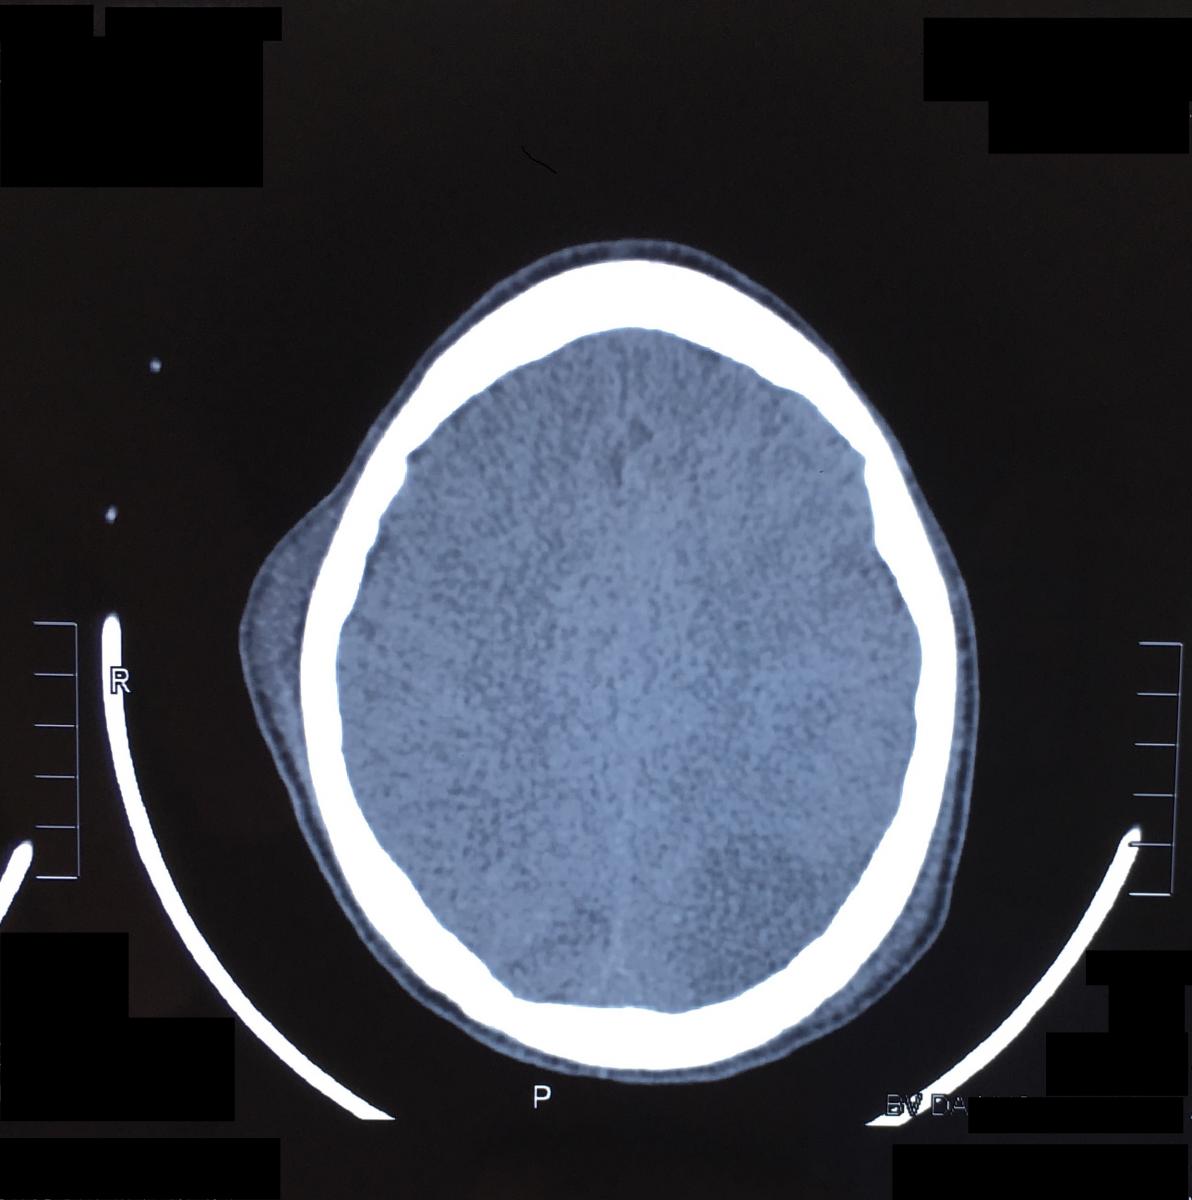

The patient was awakened and extubated successfully on the fourth postoperative day, and his Glasgow Coma Score was 15. Unfortunately, the patient suffered an ischemic lesion of left occipital lobe that was confirmed with computed tomography (CT) scan of the head (Figure 4). He had some symptoms such as imbalance, vision loss, language disorder, and swallowing reflex that were ameliorated for next 9 days, except for the swallowing reflex. The patient was given an endoscopic gastrotomy for a long-term feeding sonde. This sonde was removed successfully after nearly 3 months when the patient could eat by mouth. From that time, the patient was normal and presented neither neurological nor motor sequelae.